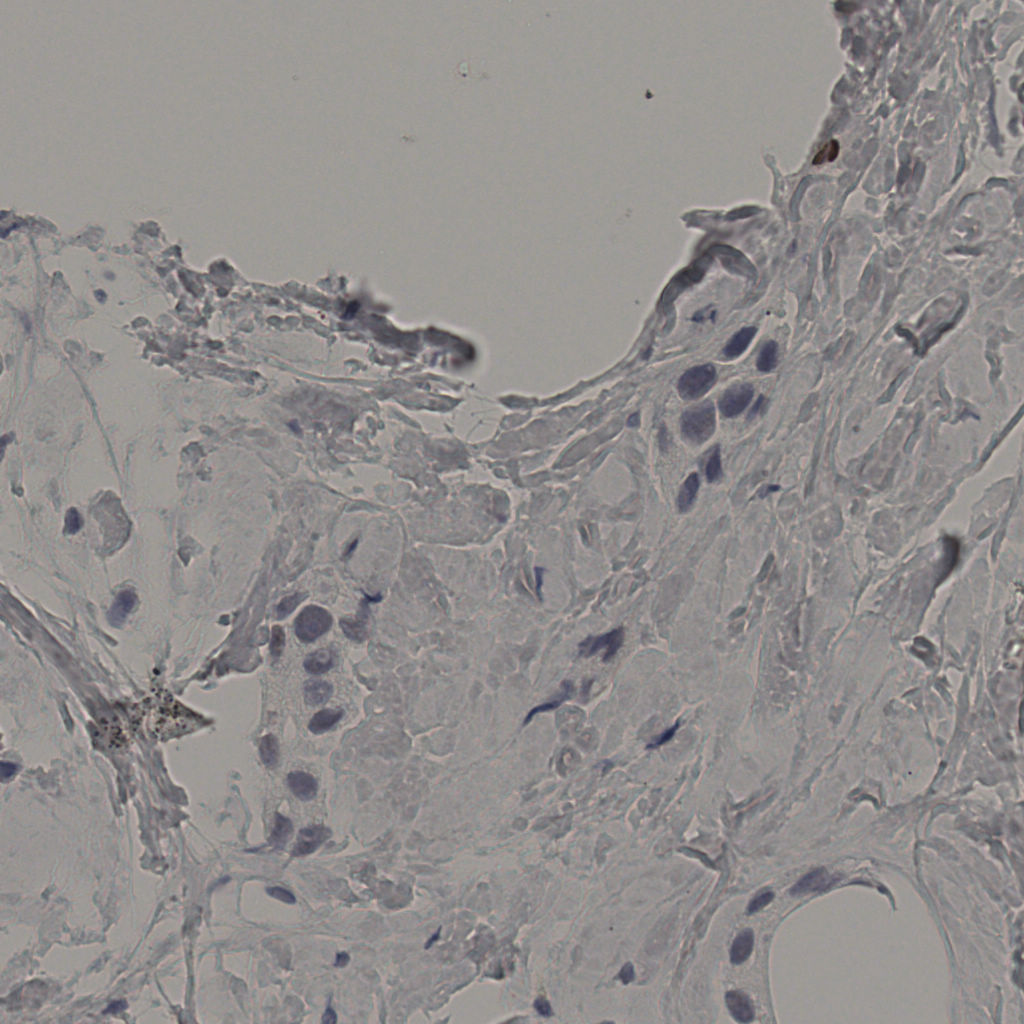

5.31%

Ki67 指数

阴 19502 阳 1093

20240398Ki-67.ndpi

slice_34_11_x30464_y9856.png

slice_34_11_x3046...